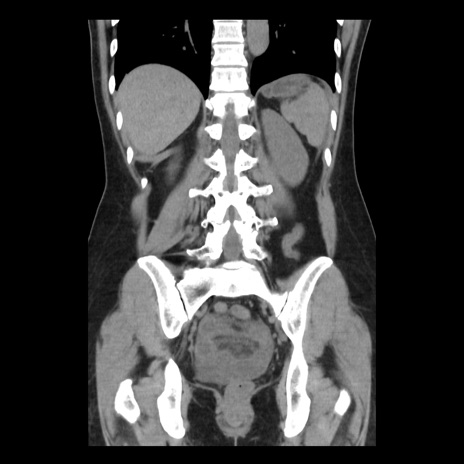

症例10(冠状断像)

【症例】 50歳代女性

【主訴】 腹痛

【現病歴】前日生レバーを食べた。今朝に排便あり。 昼前に突然発症の腹痛を生じ、当院救急外来を受診した。

【既往歴】 子宮筋腫にてで子宮全摘後

【身体所見】 意識清明、腹部:平坦、軟、下腹部やや左を中心に圧痛・反跳痛あり、筋性防御あり

【データ】WBC 7800、CRP 0.07